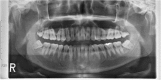

Methods: Thirty-six patients with bilateral mandibular impacted third molars based on Pell-Gregory and Winter classification were included in this study. This study was a randomized clinical trial utilizing a split-mouth design with one side assigned as collagen sponge insertion and the other side assigned as the control. Post-operative clinical complications, periodontal integrities, and radiographic outcomes were assessed at 1, 2, and 14-weeks post operatively.